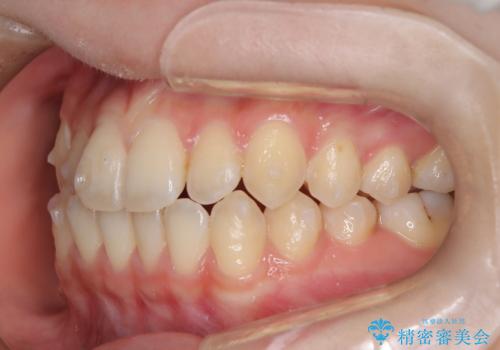

前歯のガタつき、下顎の前突感を治したい インビザライン矯正例

- 治療計画